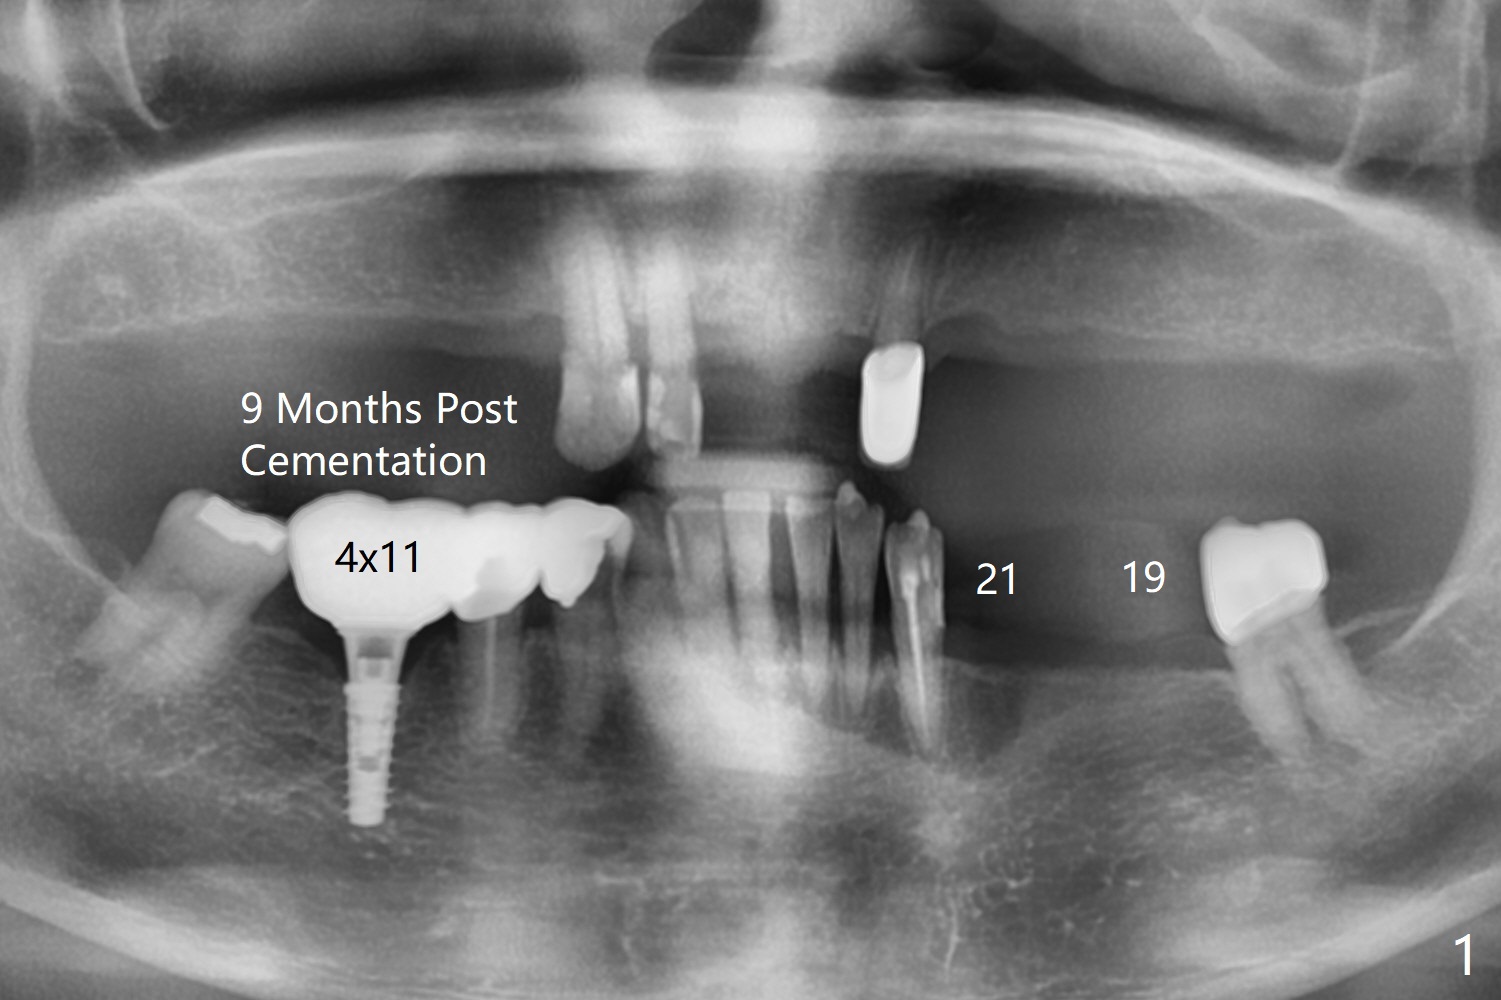

A 65-year-old woman returns for 19-21 implant FPD 9 months post cementation at #30 (Fig.1). The bone density is 600 units at #19 (Fig.2). To place a 4x10 mm implant, underdrilling is required (the last drill will be 3 mm). The implant at #21 will be expected to be 3.5x11.5 mm (Fig.3). Since the ridge at #19 and 21 is narrow (Fig.2,3 arrowheads), the keratinized gingiva should be narrow. Incision will be made to save the latter. Take photos of the erythematous ridge, as related to denture fungal infection.